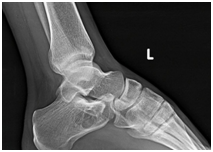

Twenty four year old male presented to us with left heel pain for nine weeks of duration. The onset of the pain was insidious and aggravated by weight bearing and prolonged standing. It was relieved with the use of analgesics and limb rest. There was no history of preceding trauma or rest pain. On examination there was no local swelling and skin changes. Deep tenderness was present over anteromedial aspect of calcaneum. Plain radiographs of the heel revealed well defined, lytic lesion in the calcaneum. Computed Tomographic scan of the same showed lytic lesion in the in the body of calcaneum just below the posterior facet. Provisional diagnosis of benign bone tumor was made and patient was planned for curettage and bone grafting.

Intraosseous lipomas are diagnosed with plain radiography and CT scan (Figure 1) (Figure 2A) (Figure 2B). Mainstay of treatment is conservative; however surgery is indicated in severe pain not responding to conservative treatment, impending pathological fracture and malignant transformation (Figure 3). Treatment for these tumors is curettage and bone grafting (Figure 4) with good prognosis.8–10

Figure 1 Plain radiograph lateral view showing lytic lesion in calcaneum.